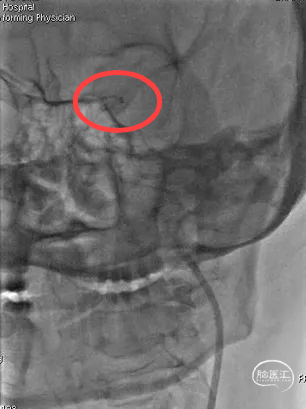

将8F导引导管送至颈内动脉起始段行负压抽吸:吸出较多粘液状血栓,复查造影颈内动脉远端未见显影。

随后将由0.014''微导丝+Rebar™ 18微导管+React™68组成的同轴系统送至靠近病变部位近端,通过React™ 68进行负压抽吸。

抽出大量粘液状栓子及少许暗红色血栓,病理报告如图:

造影证实开通,远端未见闭塞。